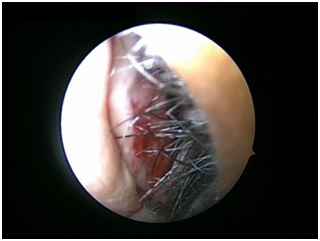

Nasal Endoscopy is done to assess the septal deviation and spurs (Figure 1) ( Figure 2). Septal infiltration is carried out with a solution of 2% Xylocaine with 1: 100,000 adrenaline in the sub-mucosal plane. It is given with a single prick at the inferior most part of the nasal septum at the junction of the septum with the floor of the nasal cavity anterior to the mucocutaneous junction. The infiltration is given at the same point on both the sides (Figure 3). The incision is always given on the deviated side. It is given anterior to the mucocutaneous junction because the skin present at that place is thick and chance of a tear of the flap is less (Figure 4). The mucoperichondrial flap is raised on the deviated side with a Freer’s elevator strictly under vision. The flap is not to be raised beyond the deviated part because the part of the septum posterior to the deviation is not under direct vision (Figure 5) (Figure 6). The caudal end of the septum is then palpated and an incision is given on the cartilage 1cm behind the columella. This 1cm of the cartilage is saved to prevent post operative tip deformities (Figure 7). The cartilage is sliced and the opposite side is entered, the mucoperichondrial flap of the opposite side is then elevated with a Freer’s elevator. A cut is given in the septal cartilage as high as possible. A septal window is created and a Ballenger’s swivel knife is taken and lodged in the place where the cartilage was cut. Creation of a septal window thus increases the area of exposure (Figure 8) (Figure 9). The flap on the non-deviated side is elevated till the bony-cartilaginous junction.

Figure 1 Deviation of septum to left side.

Figure 2 Spur present towards left side.